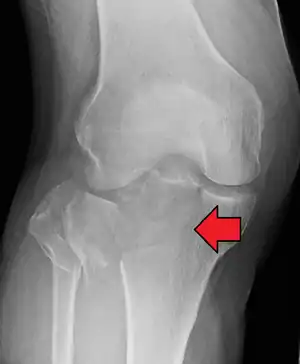

In all injuries to the tibial plateau radiographs (commonly called x-rays) are imperative. Computed tomography scans are not always necessary but are sometimes critical for evaluating degree of fracture and determining a treatment plan that would not be possible with plain radiographs.[5] Magnetic Resonance images are the diagnostic modality of choice when meniscal, ligamentous and soft tissue injuries are suspected.[6][7] CT angiography should be considered if there is alteration of the distal pulses or concern about arterial injury.

Subtle tibial plateau fracture on an AP X ray of the knee

A tibial plateau fracture seen on X-ray